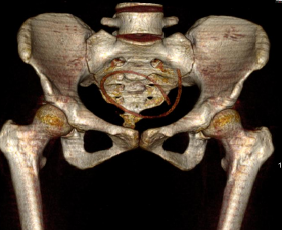

Компьютерная томография.

Позволяет достоверно выявить инородное тело в анатомически сложной области, оценить степень изменений в окружающих тканях, взаимоотношение инородного тела с прилежащими органами, а также выявить наличие возможных осложнений.

Метод выбора для выявления госсипибомы - КТ. В раннем послеоперационном периоде госсипибома наиболее достоверно диагностируется при визуализации округлого образования с губчатой внутренней структурой, с множественными пузырьками газа в структуре. При в/в контрастировании визуализируется тонкое периферическое кольцо контрастного усиления, соответствующее гранулематозному воспалению вокруг инородного тела. В позднем послеоперационном периоде госсипибома может утратить губчатую структуру и КТ-картина может быть сходна с ограниченным скоплением жидкости или с абсцессом. В отдаленном послеоперационном периоде госсипибому следует дифференцировать с новообразованиями, при этом отмечается отсутствие достоверного накопления контрастного вещества как в центральной зоне, так и стенке госсипибомы. В позднем и отдалённом постоперационном периоде также возможна кальцификация стенок госсипибомы.